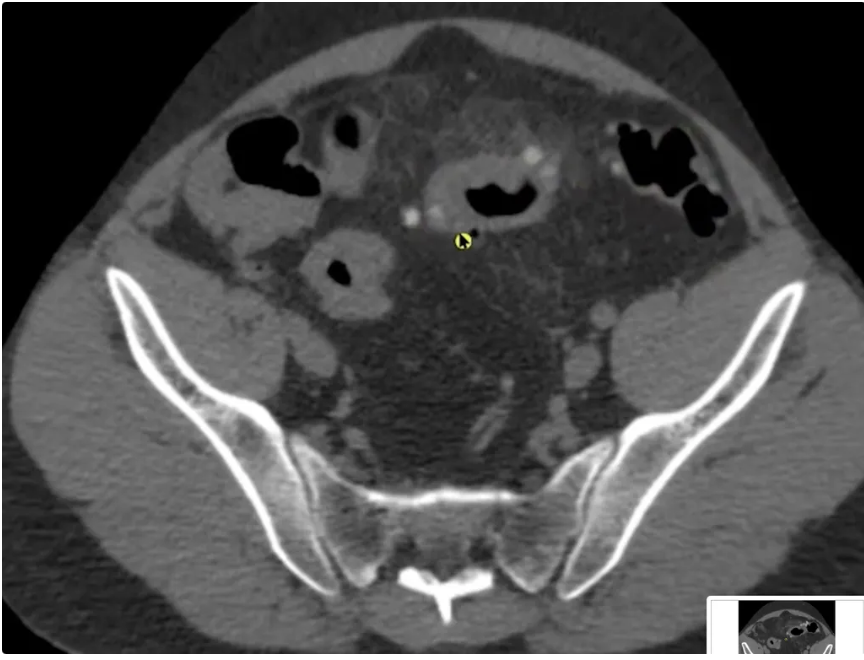

Achado?

A

DIVERTÍCULO COM AR DENTRO DELE EM CÓLON DE PAREDE ESPESSADA E BORRAMENTO DE GORDURA

12

Q